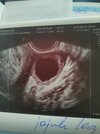

Na jednym zdjęciu mój Fasolek , a na drugim torbiel ..

Dzień dobry Kobietki , byłam wczoraj u lekarza prywatnie, lekarz znalazł na lewym jajniku dość dużą torbiel , małego krwiaka wokół pęcherzyka , w pęcherzyku jest już zarodek , prawdopodobnie młodsza ciąża niż według miesiączki , jeszcze ciężko było go zmierzyć ale słyszałam już tętno i widziałam na wykresie rytmiczne takie grube linie. Dostałam luteinę dopochwowo plus ten Duphaston. Odpowiedział na wszystkie nurtujące mnie pytania ale jeszcze nadal czuję strach po tym jak powiedział że ciąża jest młodsza niż według tej miesiączki która podałam . Czy mam się czym martwić ? Przed poronieniem również słyszałam że ciąża jest młodsza .. stąd moje obawy .